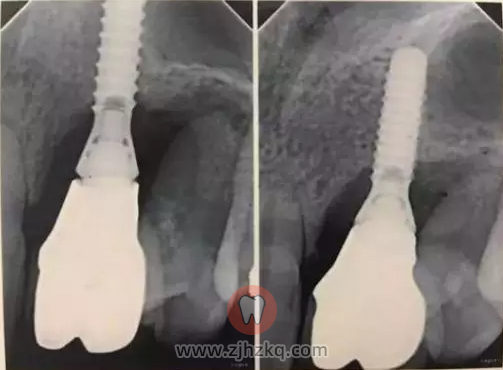

虽然种植牙已然是一项技术非常成熟,安全性也非常高的手术了,但这并不意味着种植牙适合每一位缺牙的患者。

种植前必须经过严格的健康检查,满足种植条件才能进行种植手术,如果罔顾口腔状况及自身健康,很可能会导致种牙失败。

在面对牙列缺失的患者时,医生要根据患者的自身情况判断是否适合做种植牙手术。